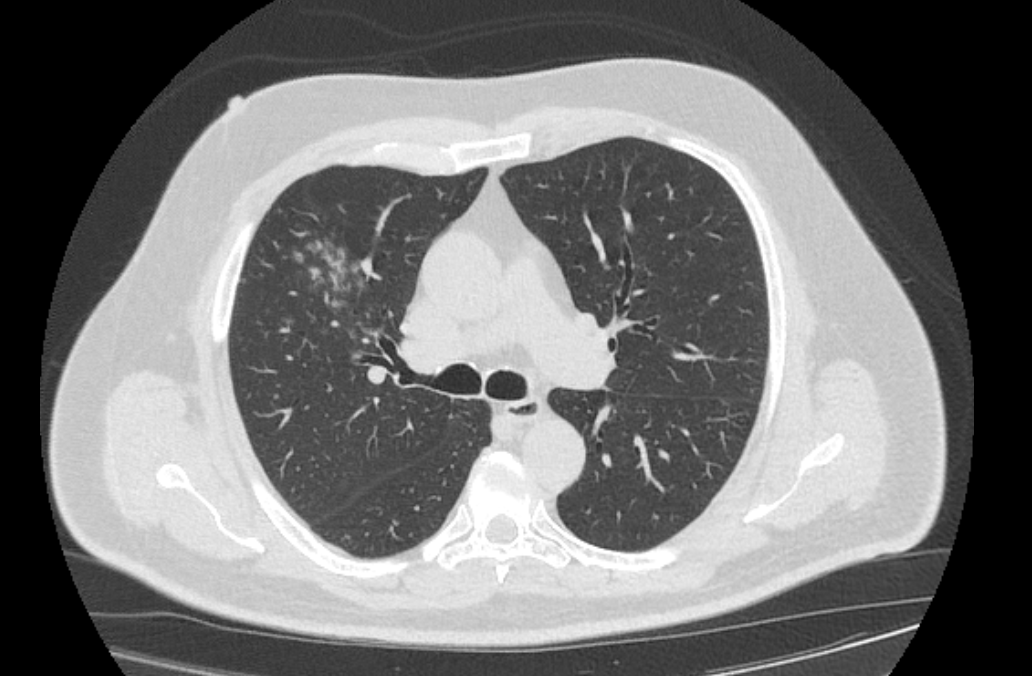

При проведении мультиспиральной КТ легких можно диагностировать различные заболевания, в том числе:

- Пневмонии (бактериальные и вирусные);

- Туберкулез легких;

- Обструктивная болезнь легких;

- Абсцесс легкого (образование полости, наполненной гноем);

- Доброкачественные новообразования в легких и бронхах;

- Рак легкого с определением стадии и распространенности процесса;

- Тромбоэмболию легочной артерии;

- Муковисцидозы, пневмофиброзы, бронхоэктазы;

- Плевриты различной этиологии;

- Врожденные аномалии.